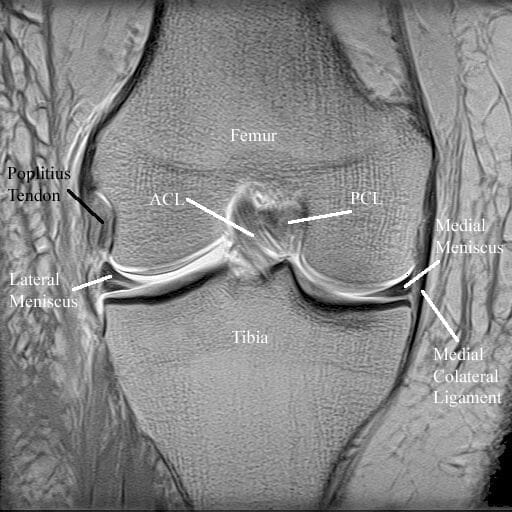

From orthopaedicprinciples.com